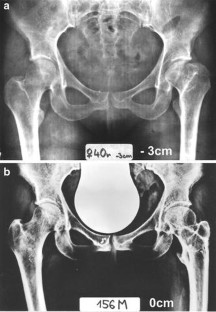

Fig. 3